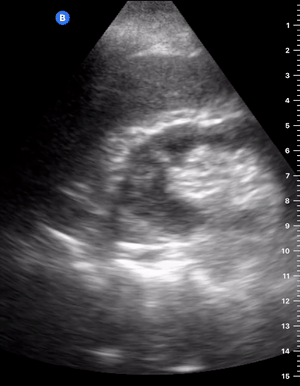

CONSOLIDATION

“If you can see the structural anatomy of lung tissue, then it is abnormal. Put simply; a non-aerated lung resembles the tissue of solid organs such as the liver. This can occur in several disease states such as collapse, consolidation, contusion, atelectasis and malignancy” (1). When scanning the lung bases, however, be aware that owing to the curved and reflective surface of the diaphragm, mirror artefacts of the liver can be seen in the normal lung area, which should not be confused with consolidation.

SHRED SIGN & AIR BRONCHOGRAM

Nontranslobar consolidations (the most common) are identified by the shred sign, where the border between the consolidated and aerated lung is irregular, drawing the fractal line. The sign indicative of translobar consolidation is the tissue-like sign (lung hepatisation). Both signs allow 90% sensitivity and 98% specificity for consolidation. The presence of pulmonary hepatisation associated with dynamic air bronchograms and focal B-lines confirms the diagnosis of pneumonia at the patient’s bedside. On the other hand, static air bronchograms are characteristic of atelectasis.